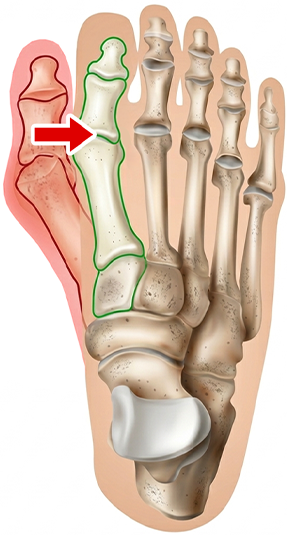

Haluksy powstają w punkcie akupunktury odpowiadającym za pracę wątroby i gruczołów, które produkują hormony odpowiedzialne za metabolizm. Efekt? Toksyny pustoszą Twój organizm, przez co nie masz energii i źle się czujesz. A do tego obrastasz w tłuszcz i tyjesz.

Gdy stopy są zdeformowane, ciężar ciała rozkłada się na nich nierównomiernie. Po kolei obciążane są stawy kolanowe, biodrowe i kręgosłup. Powstają dokuczliwe zwyrodnienia i stany zapalne, które powodują trudne do zdiagnozowania bóle.

Haluksy to deformacja, która rozwija się latami i wymaga kuracji równie zaawansowanej, co sam problem. Trwałe pozbycie się koślawego palucha i dolegliwości z tym związanych wymaga działania na 3 płaszczyznach:

Skorygowanie ustawienia palucha poprzez precyzyjny nacisk punktowy przywraca prawidłową biomechanikę stopy — ból odpuszcza, stan zapalny wygasa, a stopa zaczyna wyglądać i pracować tak, jak powinna.